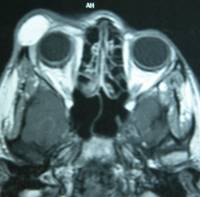

Dermoid: is a benign tumor of the conjunctiva presenting as a solid mass in the conjunctiva or near the cornea. It may be associated with other diseases. They are generally small but large ones can affect vision in which case they require surgical treatment.

| CT scan in the right eye with appearance of a white crescent corresponding to the lesion | |